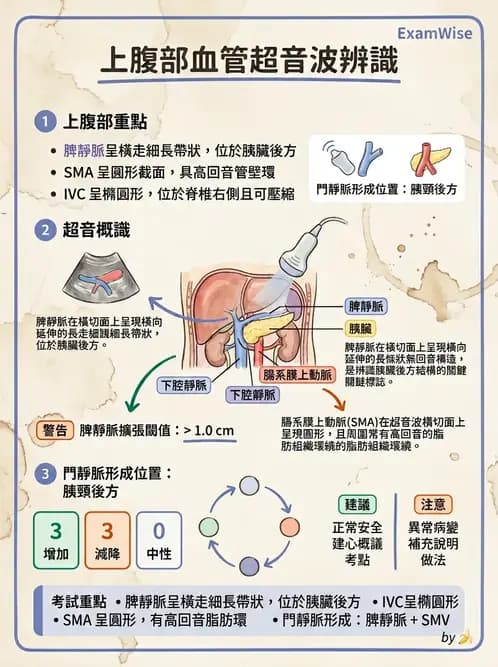

上腹部超音波血管解剖辨識,重點在於區分脾靜脈(splenic vein)、腸系膜上動脈(superior mesenteric artery, SMA)、腸系膜上靜脈(superior mesenteric vein, SMV)及下腔靜脈(inferior vena cava, IVC)等主要血管構造。

本題超音波為上腹部橫切面(transverse)掃描影像,可見多條無回音(anechoic)管狀血管構造。白色箭號指向影像左上方一條呈橫向走行的細長無回音管狀構造,其長軸方向與探頭掃描方向近乎平行,走行位置位於胰臟體部後方。

影像中可辨識以下結構:

- 中央圓形無回音結構:主動脈(aorta)及 IVC,位於中線,呈圓形或橢圓形斷面

- 主動脈前方圓形無回音結構:SMA,圓形斷面,管壁較厚(高回音壁環)

- 箭號所指橫走管狀無回音構造:脾靜脈,緊鄰並走行於胰臟體部後方,由脾門向右延伸匯入門脈,在橫切面上呈細長帶狀

脾靜脈的辨識關鍵:其走向幾乎是水平橫跨上腹部,在超音波橫切面上呈現長條形無回音帶,而非圓形截面,此點有別於 SMA(圓形截面)及 IVC(較大的橢圓形截面)。